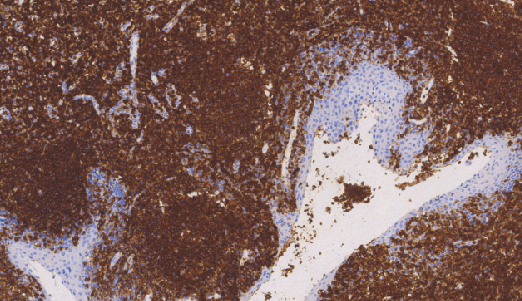

CD45(LCA)鼠抗人白细胞共同抗原(CD45)单克隆抗体

LCA(Leukocvte common Antigen)主要位于白细胞表面,包括非霍奇金氏淋巴瘤赘生的T和B淋巴细胞,正常淋巴细胞、巨噬细胞、组织细胞、名形核白细胞、单核细胞等。

- 阳性部位:胞膜

- 适用组织:石蜡切片

- 预处理:热修复